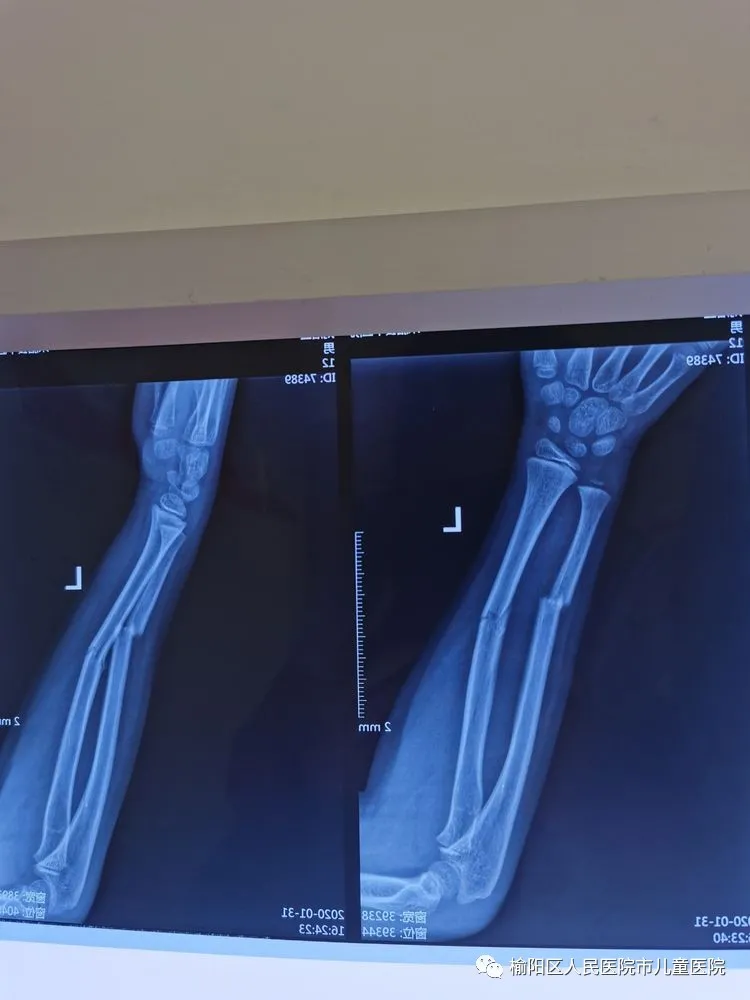

患兒12歲,因外傷致左尺橈骨骨折

復(fù)位外固定后家屬不滿意